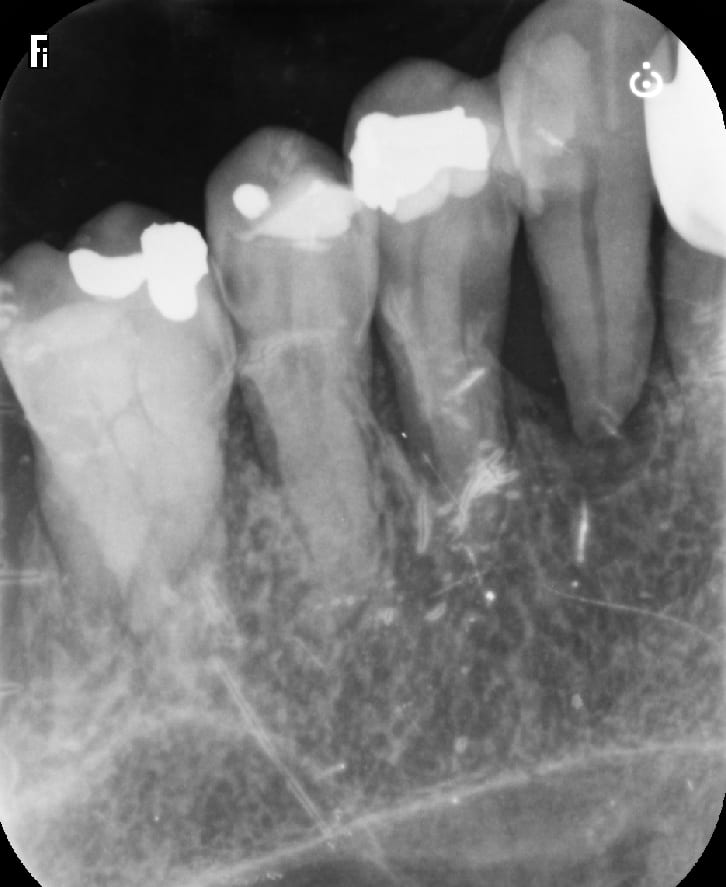

j'ai fait 2 couronnes en zircon solidarisées sur 24+25 + inter 23

autrement dit un bridge avec extension .

c est une béance avec 24 et 25 très mobile , enfin elles l étaient avant le prov .

c est un pb ce zircon full , en fait c est une grosse merde . surtout ces zircons jolis c est fragile pour les bridges .

d un autre coté , sur un cas comme ça , si tu fais de la ccm alors là c est sur que tu as un pb paro tout de suite avec perte des dents rapidement .

du coup , quoi faire d autre ? devant c est un bridge que j ai fait en 2018 et c était bien pire , en attendant les implants qu elle n a jamais fait .

le bridge ant 11.21.22 qui lui était NR , elle a pris l habitude de ne pas avoir de feuilles :-))